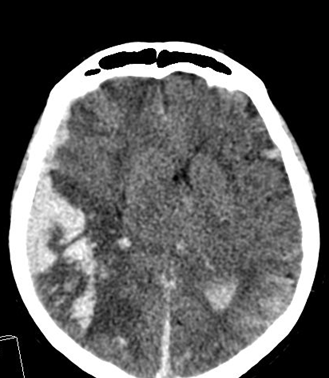

On CT images acute bleeding always presents as hyperdensity. (One has to keep it mind that hyperdensity of the blood is affected by the hematocrit levels, hence making the diagnosis more difficult.) Intraparenchymal blood is dominated by a destructive appearance (mass-effect) and it is surrounded by hypodensity as a sign of perifocal edema. It often breaks into the ventricles. In patients lying in a supine position they collect (sediment) at the occipital horn of the lateral ventricles, creating a hyperdense liquid-to-liquid levels. Later on, the density of blood decreases and shows a peripheral ring or rim-like contrast enhancement without mass-effect.

Although, subarachnoid hemorrhage (SAH) is most often caused by the rupture of a berry aneurysm, arteriovenous malformation (AVM) and trauma can also lead to it. SAH is typically located at the basal subarachnoid spaces, which then propagates along the lateral fissures or it fills up the interhemispheric fissure till the convexities. The main collection of the blood is usually indicative of the source of origin. In cases of parenchymal spread the mechanism, whether it broke in, or it broke out from the parenchyma could represent a differential diagnostic challenge. When accompanied by brain edema, the consequent herniation can result in parenchymal infarcts as well.

CT angiography examination is usually advisory in order to confirm the site of the bleeding. It is also effective when a hemorrhagic tumor is in the differentials, although complete differentiation might only be achieved by follow-up examinations. CTA is also essential in the diagnostics of multiple aneurysms (which are prevalent in 20-30% of the cases based on autopsy reports.) In case of a subarachnoid hemorrhage the consequently developing hydrocephalus and its degree might only be detected on follow-up CT examinations. It is very important to note that an initial brain aneurysm rupture might be followed by a second one within the first 7 – 10 days and the resulting vasospasm carries a much higher risk of mortality than the one at the time of the first SAH. This is why the scrutonius review of the acute diagnostic imaging is essential and it plays a fundamental role in patient treatment. Open brain surgery of the aneurysm (clipping) has been replaced by catheter angiography (DSA) nowadays. The aneurysm is either filled up with thrombogenic coils through its neck or recently bypassing stents are inserted to exclude the aneurysm from the cerebral circulation.